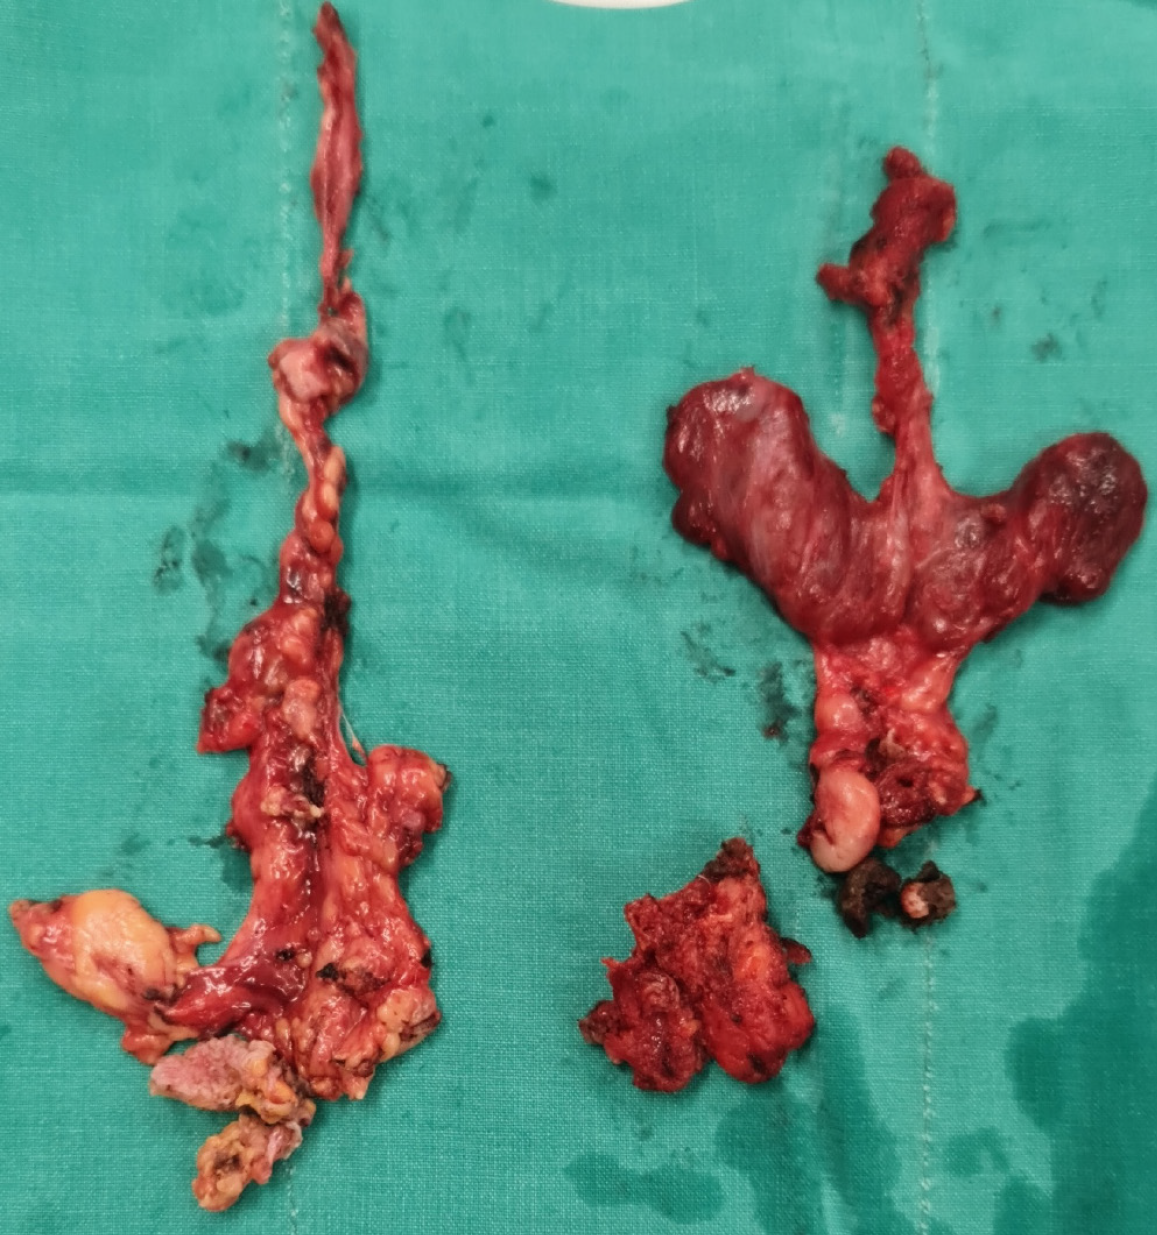

Figure 1 Surgical specimen showing extensive central (VI, VII) and right lateral (IIA, III, IV, VB) lymph node dissection (left) and the resected thyroid gland (right).